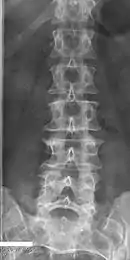

Congenital vertebral anomalies are a collection of malformations of the spine. Most, around 85%, are not clinically significant, but they can cause compression of the spinal cord by deforming the vertebral canal or causing instability. This condition occurs in the womb. Congenital vertebral anomalies include alterations of the shape and number of vertebrae.

Lumbarization is an anomaly in the spine. It is defined by the nonfusion of the first and second segments of the sacrum. The lumbar spine subsequently appears to have six vertebrae or segments, not five. This sixth lumbar vertebra is known as a transitional vertebra. Conversely the sacrum appears to have only four segments instead of its designated five segments. Lumbosacral transitional vertebrae consist of the process of the last lumbar vertebra fusing with the first sacral segment. [1] While only around 10 percent of adults have a spinal abnormality due to genetics, a sixth lumbar vertebra is one of the more common abnormalities. [2]

Sacralization of the fifth lumbar vertebra (or sacralization) is a congenital anomaly, in which the transverse process of the last lumbar vertebra (L5) fuses to the sacrum on one side or both, or to ilium, or both. These anomalies are observed in about 3.5 percent of people, and it is usually bilateral but can be unilateral or incomplete (ipsilateral or contralateral rudimentary facets) as well. Although sacralization may be a cause of low back pain, it is asymptomatic in many cases (especially bilateral type). Low back pain in these cases most likely occurs due to biomechanics. In sacralization, the L5-S1 intervertebral disc may be thin and narrow. This abnormality is found by X-ray.